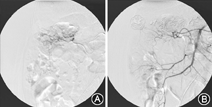

2年前,因发现排鲜红血便,伴头晕,就诊于我院。血常规示血红蛋白69 g/L,停用抗血小板药物,并给予质子泵抑制剂、生长抑素及收缩内脏血管等药物后,仍有柏油样便或暗红色血便。2013年1月25日的超声心动图检查显示:主动脉瓣显著增厚、钙化,合并重度狭窄及轻度关闭不全;左心室整体收缩功能减退;左心室舒张末期内径43 mm;左心室射血分数50%;跨主动脉瓣峰值流速4.0m/s,峰值压差64 mmHg,平均压差38 mmHg。2013年2月21日行肠系膜动脉造影,示肠系膜上动脉分支中结肠动脉及右结肠动脉染色异常,末梢血管扭曲、增多、紊乱,考虑血管动静脉畸形或肿瘤(图1)。2013年2月26日行肠镜检查,进镜至距肛门约35 cm处,可见大量陈旧血迹及血块,因患者无法耐受,终止进镜。结合主动脉瓣重度狭窄、消化道出血及肠系膜动脉造影结果,诊断为Heyde综合征。经过药物治疗后,患者大便转黄,血红蛋白维持在76 g/L左右,好转出院。出院后未再有黑便或鲜血便,多次大便常规提示隐血阳性,血红蛋白波动于63~84 g/L。